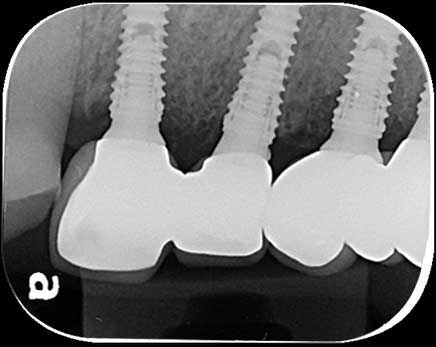

案例4